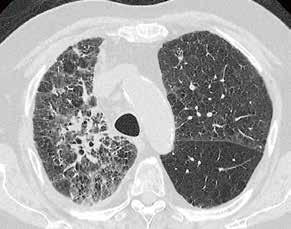

Fall 3:

Thorax-CT im Rahmen einer Lungenkrebsfrüherkennungsstudie. Die Voruntersuchung lag als externe kontrastmittelgestützte Thorax-CT vor. Bei der dosisoptimierten Low-Dose-CT liegt die Strahlenexposition nur noch im Bereich von zwei konventionellen Röntgenaufnahmen des Thorax, die Bildqualität ist für die Fragestellung nach Herdbefunden aber dennoch eindeutig ausreichend, selbst interstitielle Lungenveränderungen lassen sich hier noch beurteilen.

Prof. Dr. med. Johannes Weßling Zentrum für Radiologie, Neuroradiologie und Nuklearmedizin Abb. 3 a: kontrastmittelgestützte Thorax-CT, externe Untersuchung; DLP 216,0 mGy × cm / 3,9 mSv. Abb. 3 b: dosisoptimierte Low-Dose-Thorax-CT, Canon Aquilion Prime SP, Rekonstruktion: AiCE; DLP 13,9 mGy × cm / 0,25 mSv.

Low-Dose-Thorax-CT als Verlaufskontrolle bei Lungenkarzinom unter Immuntherapie. Aus der Anfangsphase der Implementierung von AiCE im klinischen Alltag zeigt sich bei vergleichbarer Dosis eine bessere Bildqualität mit besserer Detailauflösung im Bereich des Lungenparenchyms, hier im Bereich der strahligen Ausläufer des Tumors und an den direkt angrenzenden Bronchialstrukturen gut zu erkennen.

Fall 4: Fall 5:

Einer der ersten Patienten, die nach der Installation der AiCE-Algorithmen untersucht wurden. Hier wurde zum Vergleich aus derselben Untersuchung jeweils eine Rekonstruktion mittels AIDR 3D und eine Rekonstruktion mit AiCE angefertigt. Auch hier fällt die bessere Detailauflösung, beispielsweise im Bereich der Interlobulärsepten oder der Emphysembullae, auf. //

Abb. 5 a: Low-Dose-Thorax-CT, Canon Aquilion Prime SP, Rekonstruktion: AIDR 3D; DLP 115,8 mGy × cm / 2,1 mSv Abb. 4 a: Low-Dose-Thorax-CT, Canon Aquilion ONE, Rekonstruktion: AIDR 3D; DLP 55,1 mGy × cm / 1,0 mSv Abb. 5 b: dieselbe Untersuchung, Rekonstruktion: AiCE Abb. 4 b: Low-Dose-Thorax-CT, Canon Aquilion Prime SP, Rekonstruktion: AiCE; DLP 65,7 mGy × cm / 1,2 mSv